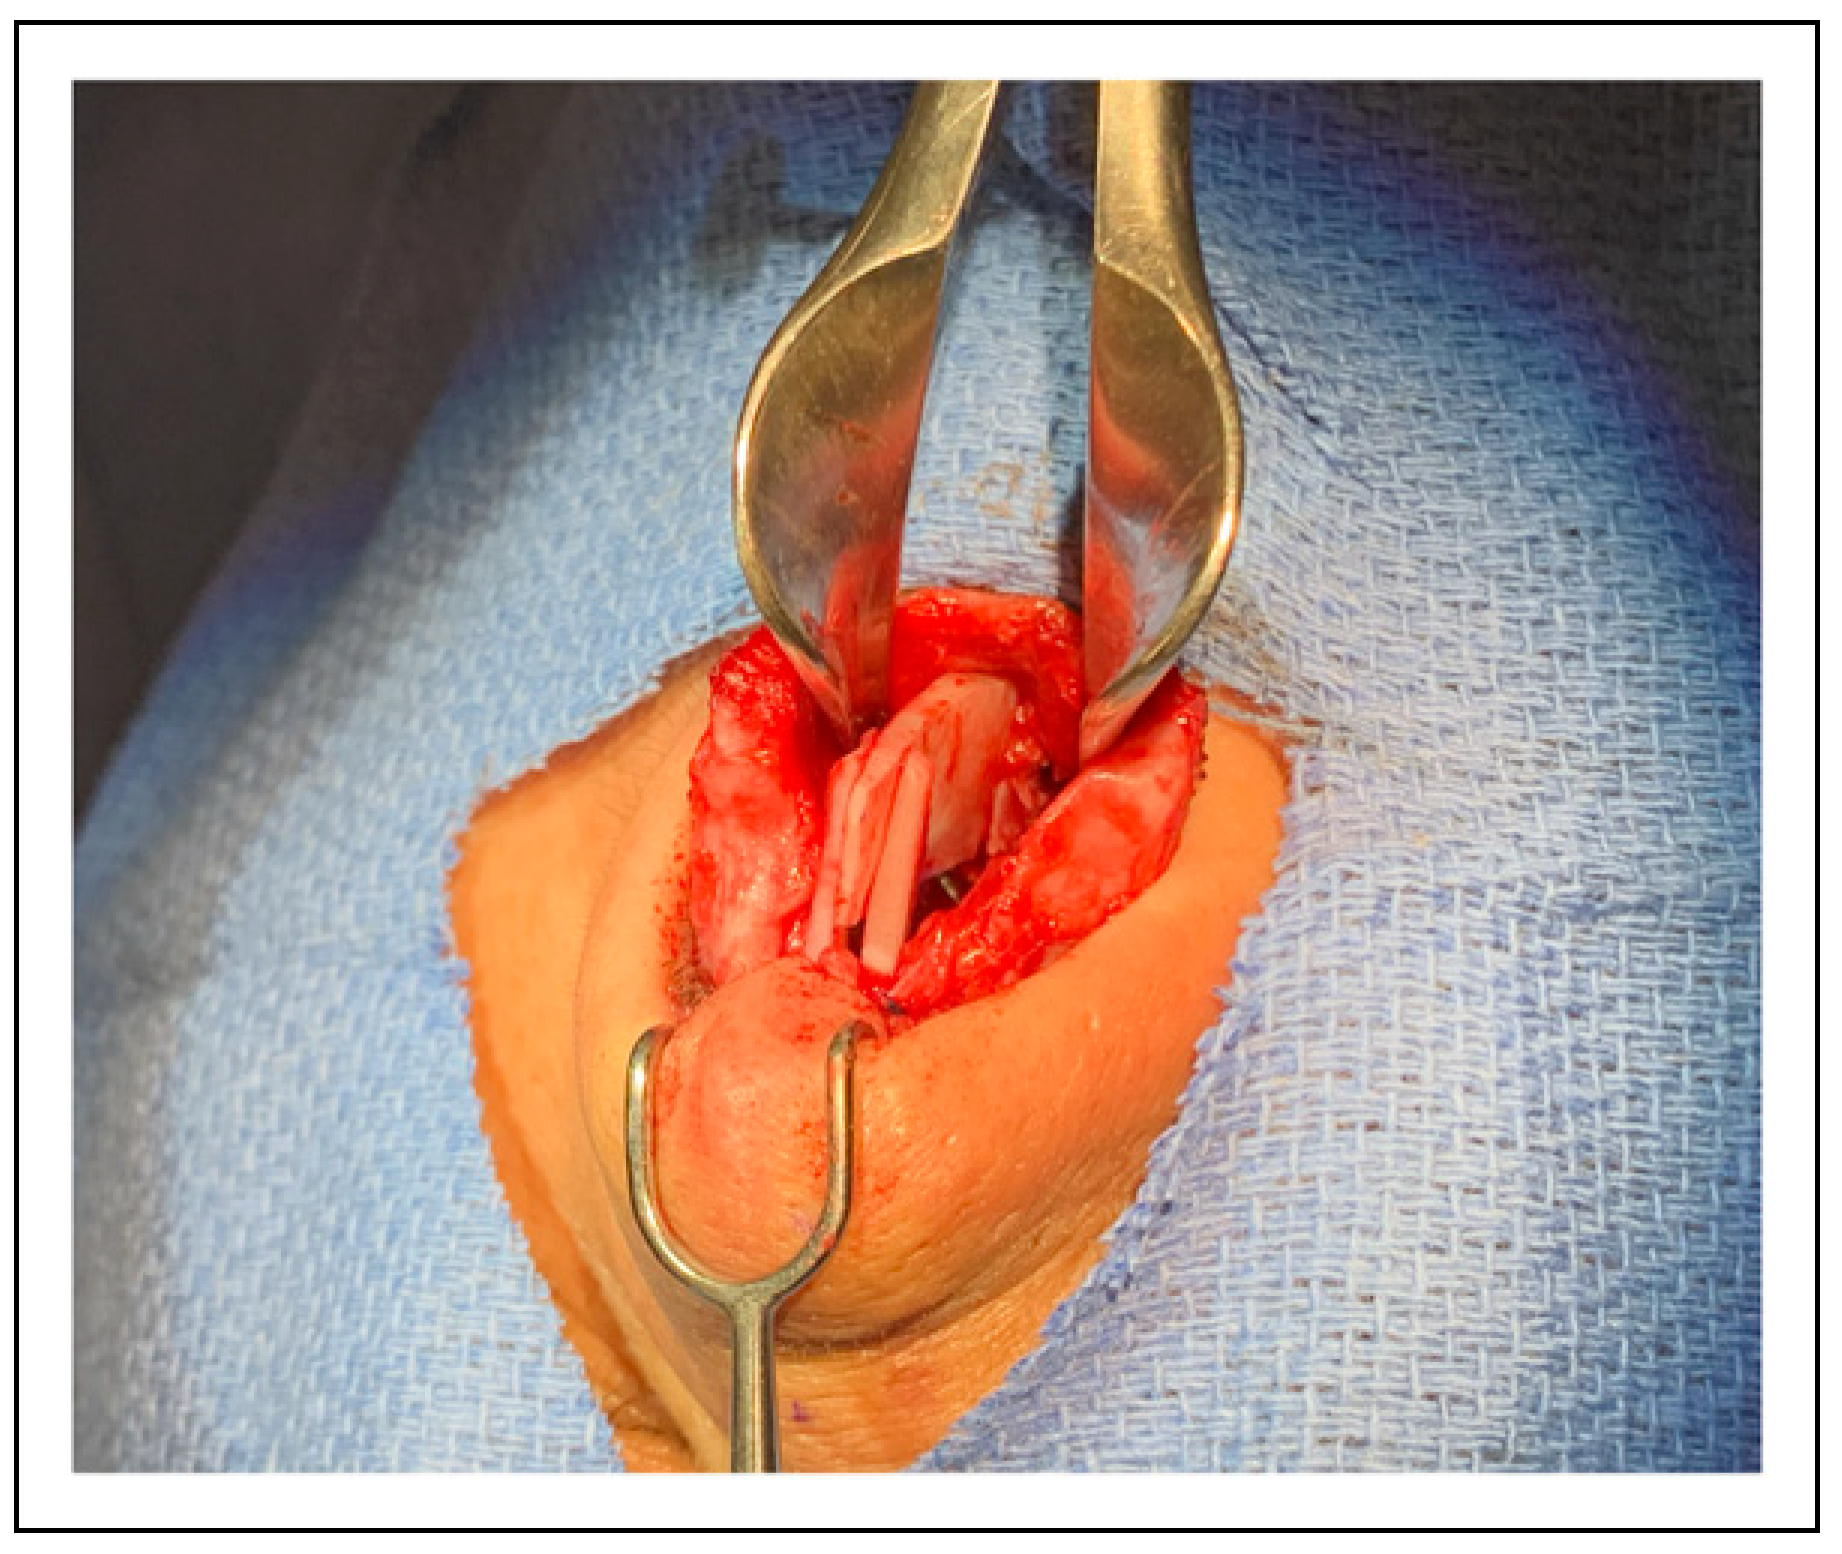

The maxillary spine was found to be shifted 4 mm to the left side away from the upper lip midline (Figure 2). Using the straight piezo saw, maxillary osteotomy was performed creating a rectangular en-bloc harboring the ANS and an ostectomy of 3 mm was performed on the right side. Care was taken to avoid injury to the neurovascular bundle of the upper incisors (Figure 3). This resulted in a mobile ANS allowing its relocation to settle in the midline. For stability, the relocated ANS was fixed in place using two .5 mm microplates and four 3.5 mm screws. This was performed by taking the ANS on the side table for precise drilling and application of bilateral microplates and screws (Figure 4). The spine was repositioned back on the premaxilla and fixation was completed. The straightest possible portion of the septal cartilage was fashioned into an ASR graft and placed on the newly positioned ANS. Two extended spreader grafts were sutured in place and fixed to the ASR graft (Figure 5 and Figure 6). A tongue-in-groove suture was taken to adjust tip rotation and achieve tip support as described previously [15]. The upper lateral cartilages were repaired and fixed to the nasal dorsum. The hemitransfixation, marginal, and transcolumellar were closed in a standard fashion. Nasal tip position, nostril symmetry, and columella were all checked. As well as adequate contour and tip support. Bilateral Doyle splints were placed, and standard taping and splinting were applied.

Figure 2. The anterior nasal spine is shifted to the left side. The light blue structure is the preserved dorsal septal strut.